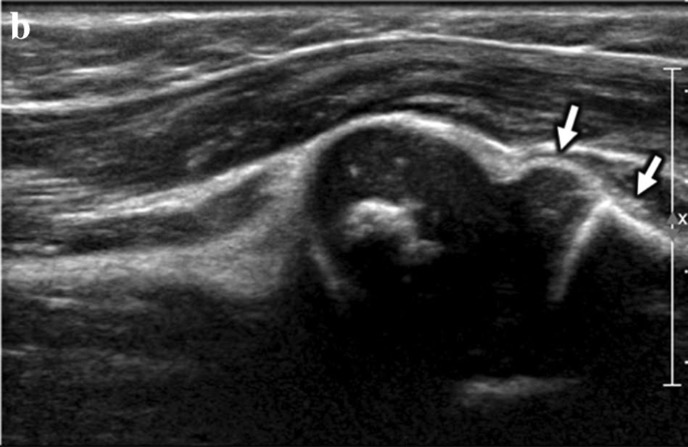

B. Le bras droit non affecté démontre une apposition chondrale normale et un positionnement normal du ligament annulaire (flèches blanches).